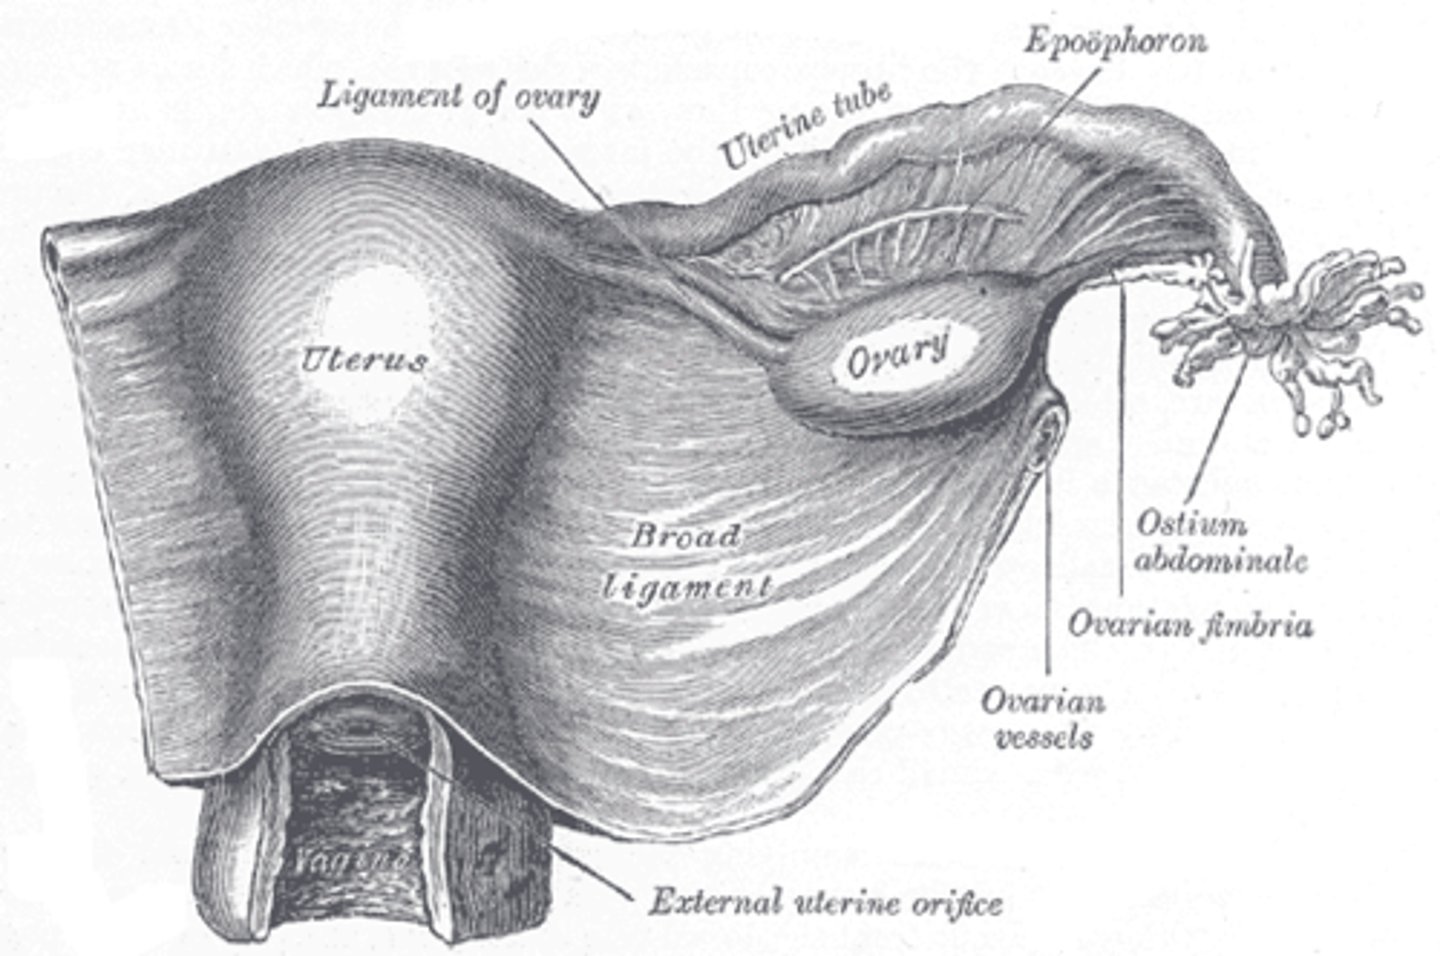

The broad ligaments extend between the ___ and ___

uterine body; ovary

What is positioned between the 2 layers of the broad ligaments?

fallopian tubes

round ligament

ovarian ligament vascular structures

The round ligaments are located ___ to the fallopian tubes and insert into the ___ to help maintain the ___ of the uterus

anteroinferior; labia majora; position

The ovarian ligaments are located ___ at the ___ of the uterus

bilaterally; cornua

The suspensory ligaments extend from the ___ to the ___

infundibulum; pelvic sidewall